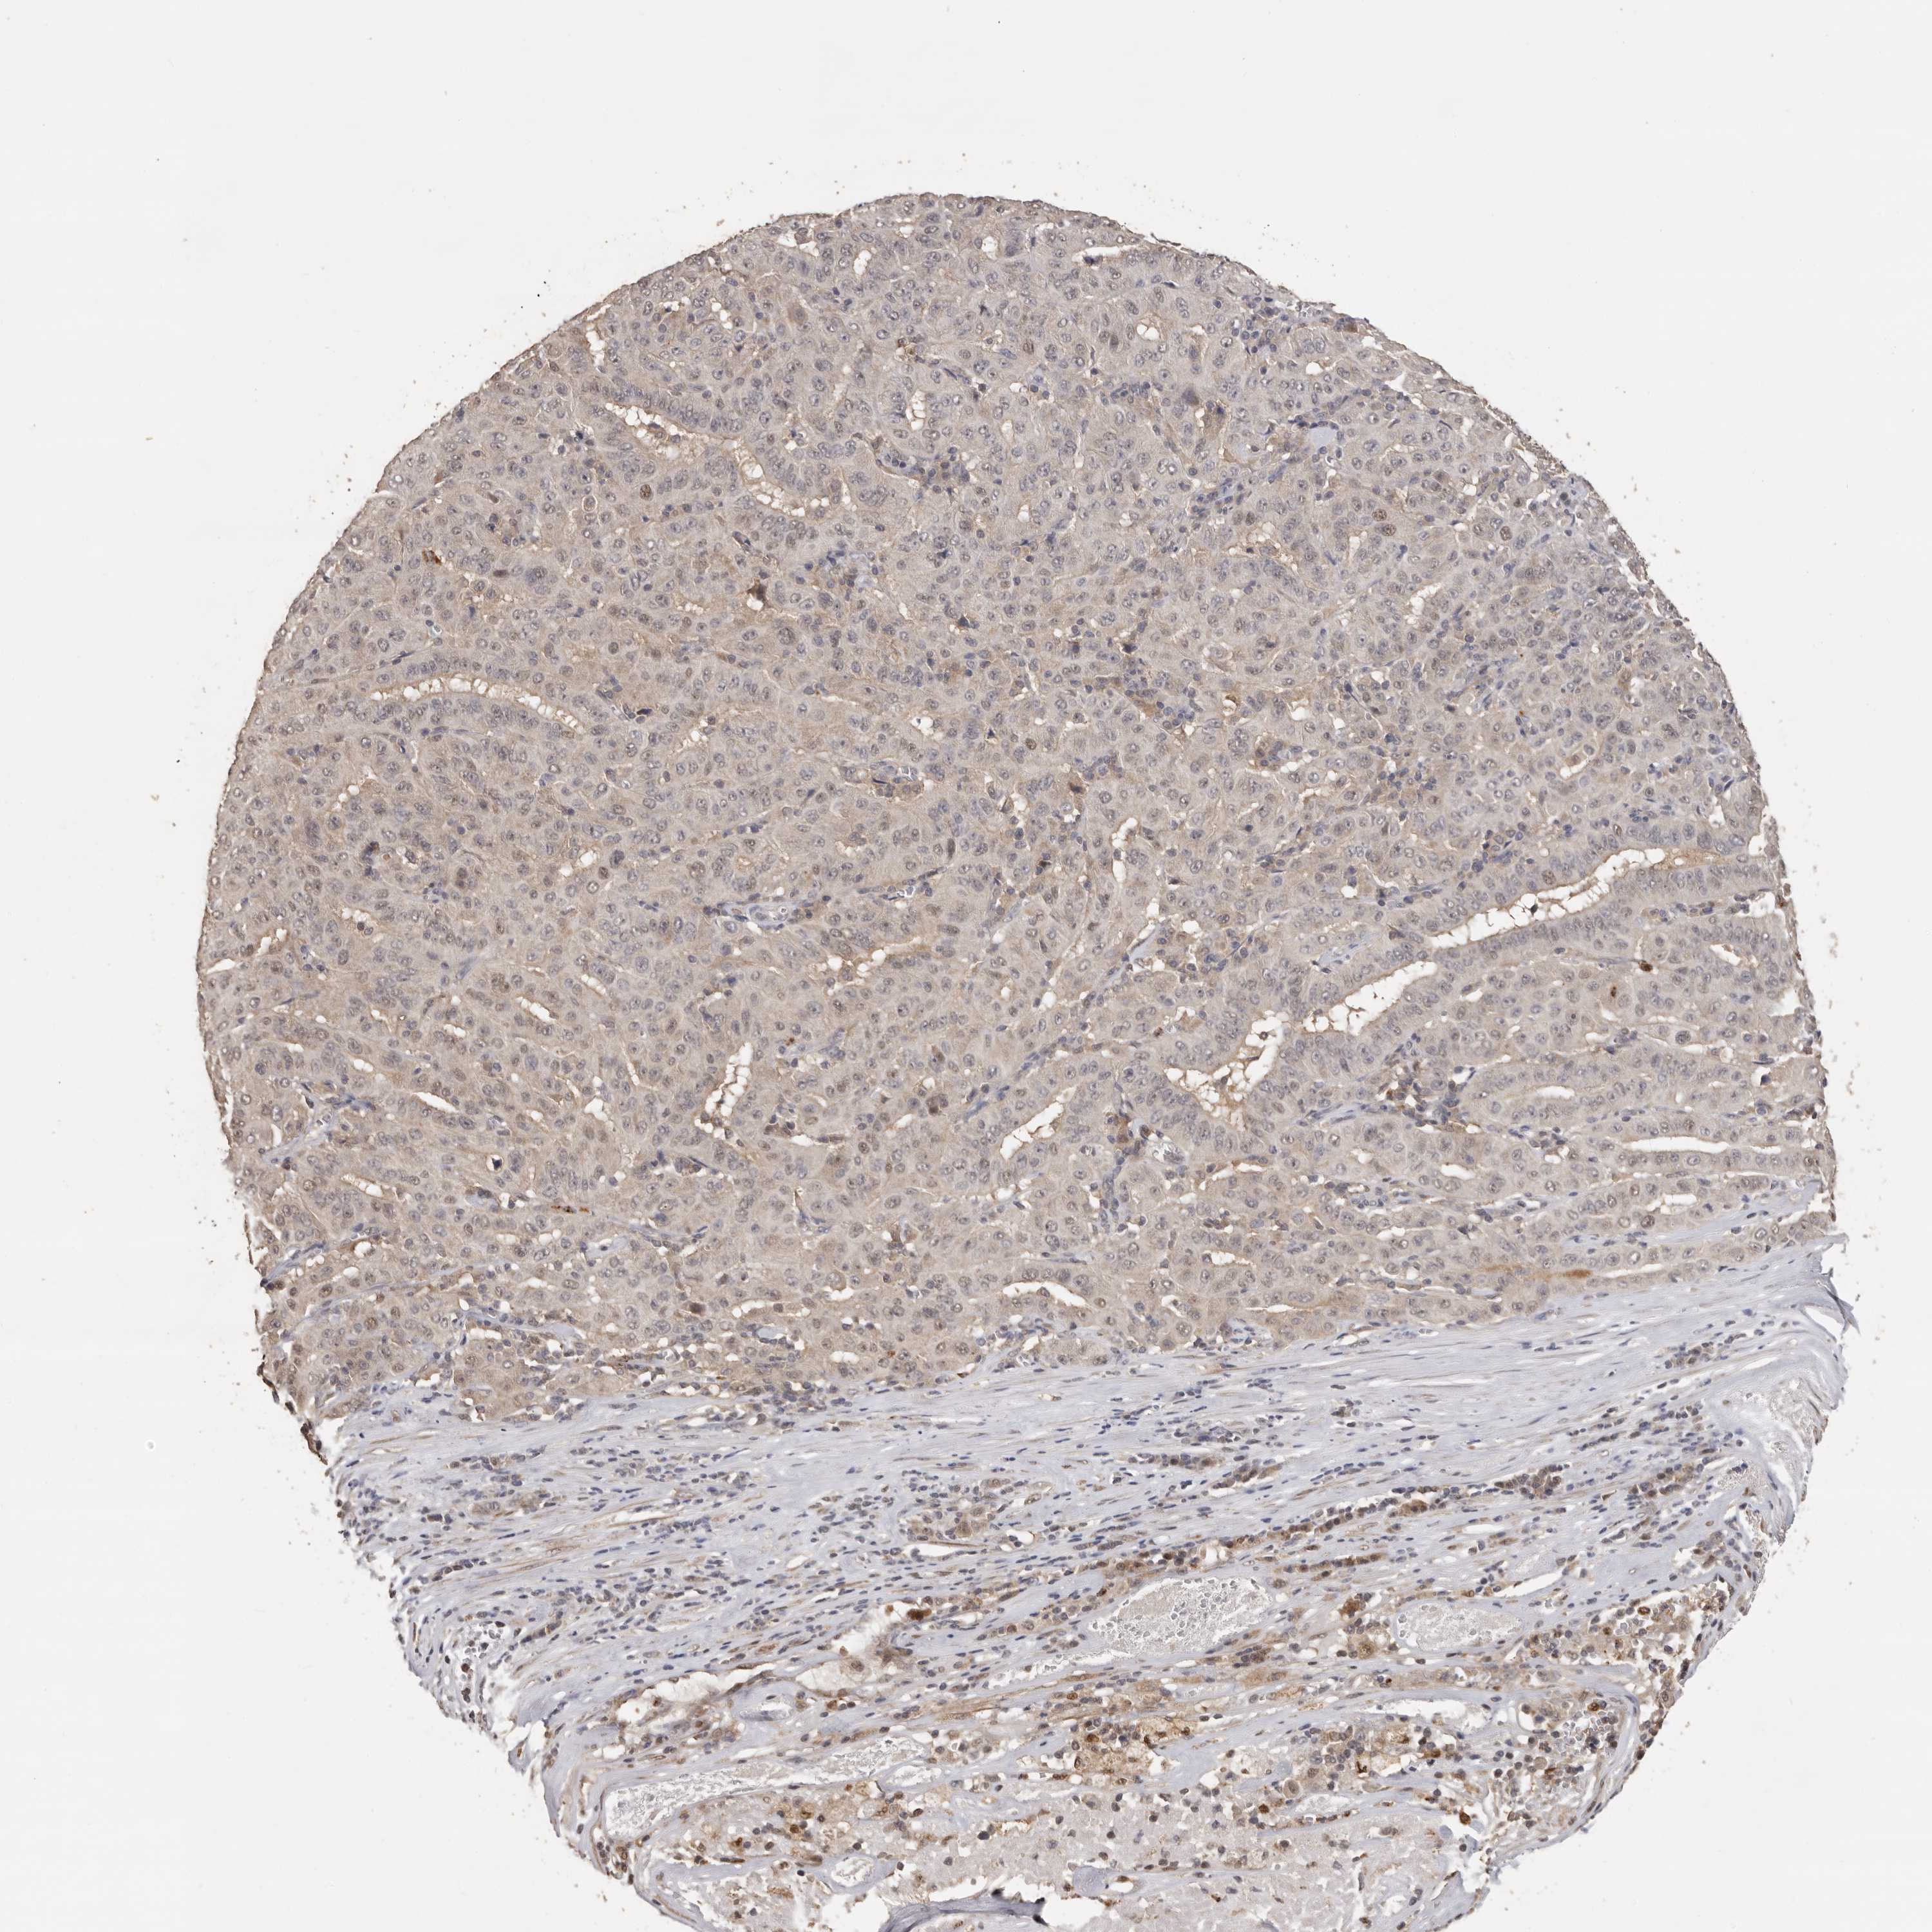

PANCREATIC CANCER - Protein expressioni

A mouse-over function shows sample information and annotation data. Click on an image to view it in a full screen mode. Samples can be filtered based on level of antibody staining by selecting one or several of the following categories: high, medium, low and not detected. The assay and annotation is described here.

Note that samples used for immunohistochemistry by the Human Protein Atlas do not correspond to samples in the TCGA dataset.

Antibody stainingi

Antibody staining in the annotated cell types in the current human tissue is reported as not detected, low, medium, or high, based on conventional immunohistochemistry profiling in selected tissues. This score is based on the combination of the staining intensity and fraction of stained cells.

Each image is clickable and will lead to virtual microscopy that enables deeper exploration of all samples and also displays staining intensity scores, fraction scores and subcellular localization as well as patient and tissue information for each sample.

Antibody HPA023081

Antibody HPA023103

Antibody HPA024795

Staining

High

Medium

Low

Not detected

Intensity

Strong

Moderate

Weak

Negative

Quantity

>75%

75%-25%

<25%

None

Location

Nuclear

Cytoplasmic/membranous

Cytoplasmic/membranous,nuclear

Adenocarcinoma, NOS